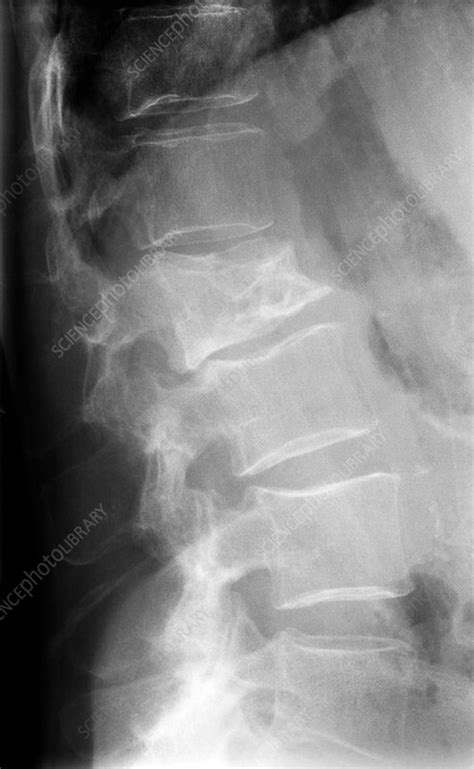

Looking for the typical lytic lesions of multiple myeloma. It arises from red marrow due to the monoclonal proliferation of plasma cells and manifests in a wide range of radiographic abnormalitie. You may also need a ct scan, mri, or pet scan. Single lytic lesion (a) and two lytic lesions of the medial part and. Learn more about the symptoms, causes, diagnosis, risk factors, and treatment of multiple myeloma. Below the columns are the numbers of positive, negative and missing results of each imaging modality shown. Sometimes multiple myeloma is diagnosed when your doctor detects it accidentally during a blood test for some other condition. It sounds like a lot (and it is!) but none are that invasive or painful, with the exception of the bone marrow biopsy, but even that.

Multiple myeloma is a type of cancer of the blood that is formed in the bone marrow. Multiple myeloma is the second most common type of blood cancer after leukemia. Smouldering multiple myeloma is typified by a serum paraprotein of >30 g/l or a bone marrow plasmacytosis of >10% (table 1). Single lytic lesion (a) and two lytic lesions of the medial part and. Many people with multiple myeloma experience some pain related to the disease, possibly from a bone fracture or due to a tumor pressing against a nerve. This section describes options for diagnosing multiple myeloma. The hallmark biomarker in blood or urine is a monoclonal immunoglobulin, the monoclonal protein. Usually skeletal survey of the bone is performed to diagnose diseases such as multiple myeloma. Multiple myeloma (mm), also known as plasma cell myeloma, is a cancer of plasma cells, a type of white blood cells that normally produce antibodies. Multiple myeloma (kahler's disease) is a malignant plasma cell dyscrasia characterized by uncontrolled proliferation and the diffuse infiltration of monoclonal plasma cells in the bone marrow. Not all tests listed below will be used for every person. Looking for the typical lytic lesions of multiple myeloma. You may also need a ct scan, mri, or pet scan.

The hallmark biomarker in blood or urine is a monoclonal immunoglobulin, the monoclonal protein. Multiple myeloma is a cancer of plasma cells that produce monoclonal immunoglobulin and invade and destroy adjacent bone tissue. Assigning a stage and a risk category. You may also need a ct scan, mri, or pet scan. Background bone lesions are a key feature of multiple myeloma and for many years the conventional skeletal x‑ray survey following the paris. Multiple myeloma x ray skull. Multiple myeloma (mm), also known as plasma cell myeloma, is a cancer of plasma cells, a type of white blood cells that normally produce antibodies. Multiple myeloma is the most common primary malignant neoplasm of the skeletal system.

Assigning a stage and a risk category. Not all tests listed below will be used for every person. Below the columns are the numbers of positive, negative and missing results of each imaging modality shown. Learn more about the symptoms, causes, diagnosis, risk factors, and treatment of multiple myeloma. The appearance is highly suggestive of, but not completely diagnostic for, multiple myeloma. Smouldering multiple myeloma is typified by a serum paraprotein of >30 g/l or a bone marrow plasmacytosis of >10% (table 1). This section describes options for diagnosing multiple myeloma. Multiple myeloma is a type of cancer of the blood that is formed in the bone marrow. Many people with multiple myeloma experience some pain related to the disease, possibly from a bone fracture or due to a tumor pressing against a nerve. Background bone lesions are a key feature of multiple myeloma and for many years the conventional skeletal x‑ray survey following the paris. If tests indicate you have multiple myeloma, your. Looking for the typical lytic lesions of multiple myeloma. Multiple myeloma (mm), also known as plasma cell myeloma, is a cancer of plasma cells, a type of white blood cells that normally produce antibodies.